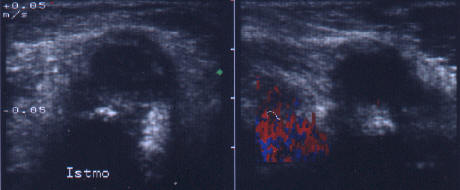

Lob stang, proiectie longitudinala.

Lob drept, proiectie longitudinala.

Acelasi

pacient. La doppler color, vascularizatie bogata, difuza in toata glanda

Femeie de 44 ani. Tireotoxicoza in m. Graves.

Marcata crestere a velocitatii cu picul sistolic (1,44 m/s).